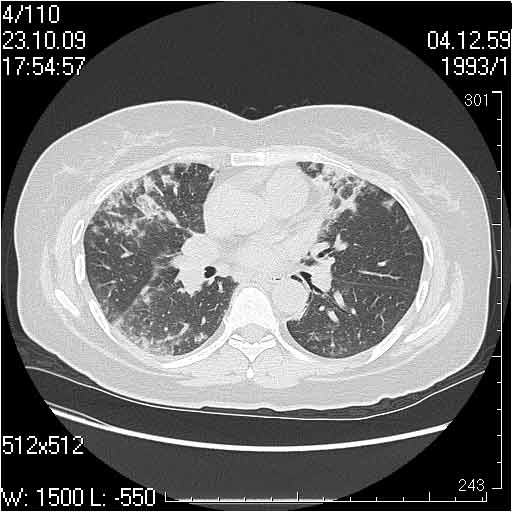

Случай №2

Мужчина 54 лет

Случай 2: картина патологических изменения довольно типична: GGOs & thickened interlobular septas = "crazy paving" sign. Наличие плотностей по типу матового стекла в сочетании с утолщением междолевых перегородок, даёт признак булыжной мостовой; на первом месте будет стоят диагноз альвеолярных протеиноз.